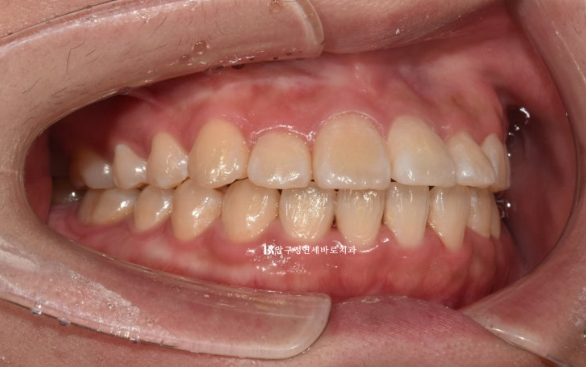

3개월에 걸쳐 14개의 첫 세트 치료를 마무리 한 후 모습입니다.

앞니 뻗침이 많이 개선이 되었지만 앞니를 조금 뒤로 더 넣고 싶다 라는 환자분의 요구에 부응하여 추가장치 제작에 들어갔습니다.

23.08